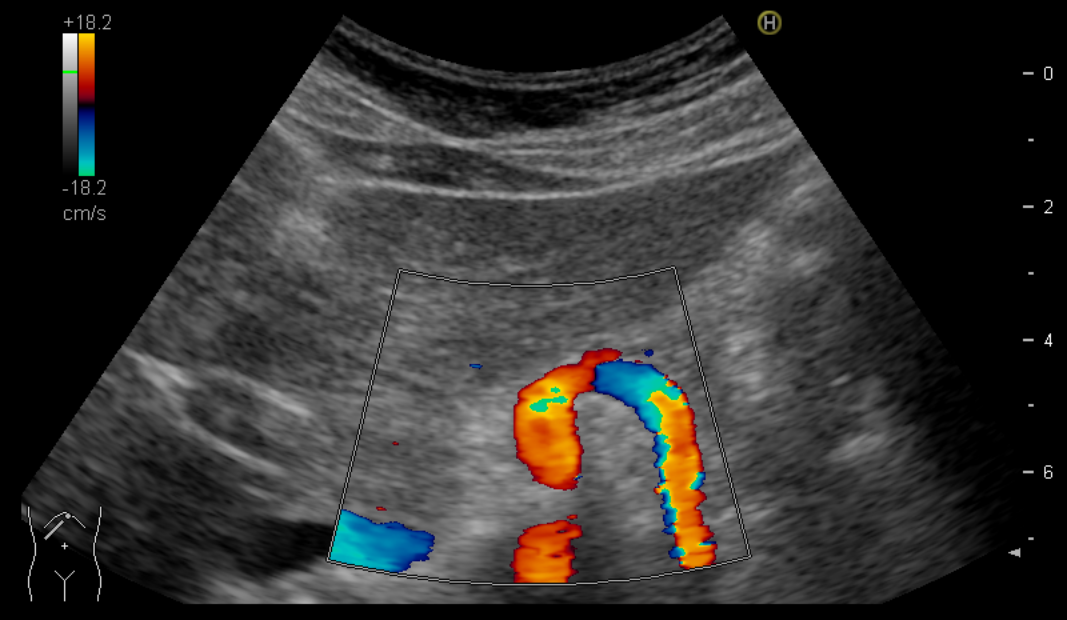

(Ch:02) Ultrasound of the LiverDecember 27, 2020(Ch:01) Physical Principles of Medical UltrasoundDecember 28, 2020 Student Image Challenge 78 Student Image Challenge #78 1 / 1 Student Image Challenge #78 It’s beginning to look a lot like Christmas. Name the candy cane! Superior mesenteric artery Left gastric artery Splenic artery Splenic vein Hepatic artery Incorrect ....Please see the correct answer highlighted Correct! Splenic artery Your score isThe average score is 35% LinkedIn Facebook VKontakte 0% Restart quiz Case courtesy of Prof Adrian Saftoiu EFSUMBAdmin Related postsStudent Image Challenge 107Read more Comments are closed.